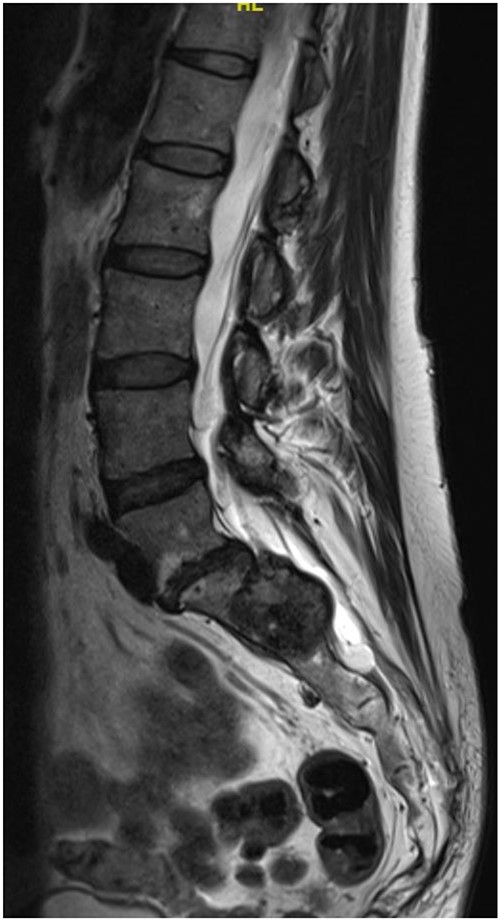

Reviews in July 2019 (with an MRI scan in December 2019) and December 2020 confirmed no neurological deterioration but some increased back and leg pain when standing for some time. A repeat MRI scan confirmed an increase in the size of the lesion (Figs 1 and 2). A biopsy was arranged with a plan for a follow-up surgery. Results of the CT-guided biopsy indicated a diagnosis of metastatic malignant melanoma. Discussions with the patient did not localise any skin lesion responsible for the metastatic deposit, an F18-fluorodeoxyglucose positron emission tomography (18F-FDG PET/CT) scan and a conventional computed axial tomography (CT) scan was organised (April 2021), which revealed sacral destruction and no other deposits in the chest, abdomen and pelvis (Figs 3 and 4). Our patient had a reported SUV of 3.6, indicating a malignant lesion that was then confirmed operatively.

At a further review (November 2018), a contrast MRI scan was requested at a follow-up in early November for 3 months post-index scan. At the follow-up, a left S1/S2 sacral tumour (most possibly schwannoma) with no change in the size was diagnosed. Repeat physical examination confirmed status quo on the neurological deficit. The decision was to review after 12 months as the patient remained stable.